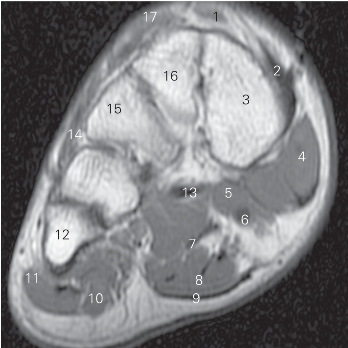

图5-51 经楔骨远段的横断层MR T1加权图像

1

长伸肌腱tendon of extensor hallucis longus

2 胫骨前肌腱tendon of tibialis anterior 3 内侧楔骨 medial cuneiform bone

4

收肌 adductor hallucis 5

短屈肌 flexor hallucis brevis

6

长屈肌 flexor hallucis longus 7 趾长屈肌 flexor digitorum longus

8 趾短屈肌 flexor digitorum brevis 9 足底腱膜 plantar fascia

10 小趾短屈肌 flexor digiti minimi brevis

11 小趾展肌 abductor digiti minimi 12 第五跖骨 5th metatarsal bone

13 腓骨长肌腱 peroneus longus tendon

14 趾短伸肌 extensor digitorum brevis

15 外侧楔骨 lateral cuneiform bone

16 中间楔骨 intermediate cuneiform bone

17 趾长伸肌 extensor digitorum longus